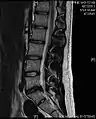

• Magnetic resonance imaging is the gold standard study for confirming a suspected LDH. With a diagnostic accuracy of 97%, it is the most sensitive study to visualize a herniated disc due to its significant ability in soft tissue visualization. MRI also has higher inter-observer reliability than other imaging modalities. It suggests disc herniation when it shows an increased T2-weighted signal at the posterior 10% of the disc. Degenerative disc diseases have shown a correlation with Modic type 1 changes. When evaluating for postoperative lumbar radiculopathies, the recommendation is that the MRI is performed with contrast unless otherwise contraindicated. MRI is more effective than CT in distinguishing inflammatory, malignant, or inflammatory etiologies of LDH. It is indicated relatively early in the course of evaluation (<8 weeks) when the patient presents with relative indications like significant pain, neurological motor deficits, and cauda equina syndrome. Diffusion tensor imaging is a type of MRI sequence used for detecting microstructural changes in the nerve root. It may be beneficial in understanding the changes that occur after herniated lumbar disc compresses a nerve root, and might help in differentiating the patients that need surgical intervention. In patients with a high suspicion of radiculopathy due to lumbar disc herniation, yet the MRI is equivocal or negative, nerve conduction studies are indicated.[44] T2-weighted images allow for clear visualization of protruded disc material in the spinal canal.